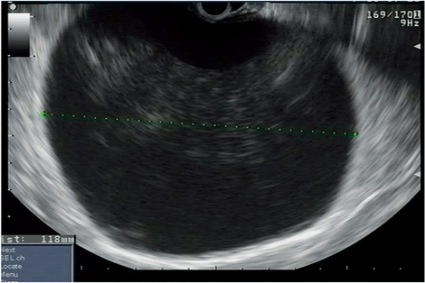

Undersökningen går till på samma sätt som en ordinär gastroskopi med samma förberedelser, och den tar mellan 15 och 60 minuter att genomföra. Elastografi är under utveckling och skulle kunna underlätta tumördiagnostiken genom bedömning av vävnaders konsistens (Figur 2).